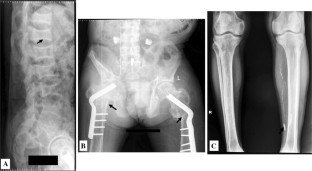

Fig. 2